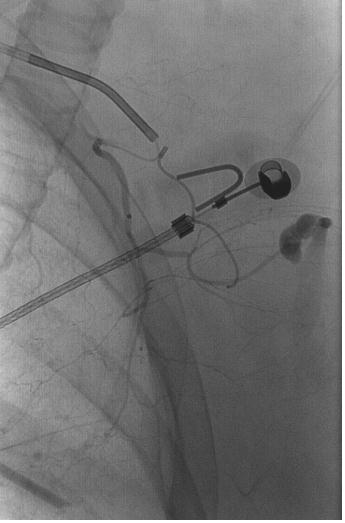

外伤后出血的栓塞

外伤后可见造影剂外溢 |

微导管选择至出血血管 |

出血血管的微弹簧栓子栓塞 |

栓塞后造影 |